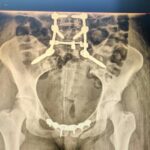

Kobiecie groziło porażenie i niedowład kończyn dolnych, ponieważ niestabilne, połamane kości mogły urazić i uszkodzić dalej rdzeń kręgowy. Jak dodaje Rafał Wójcicki, w trakcie kilkugodzinnej operacji, udało się połączyć kręgosłup z miednicą i zespolić miednicę.

– Stwierdziliśmy, że jest możliwość wykonania zabiegu połączenia i ustabilizowania kręgosłupa lędźwiowego z miednicą i jednocześnie zespolenie kości miednicy. Operacja udała się, a trwała około 5 godzin. Dzięki temu pacjentka może być rehabilitowana i wracać do zdrowia. Myślę, że wszystko dobrze się skończy. Bez tej operacji nie można było pacjentki w ogóle spionizować i myśleć o chodzeniu- dodał Rafał Wójcicki.

Pacjentka w trakcie operacji ułożona była w dwóch różnych pozycjach. Lekarze wykorzystali implanty do kręgosłupa i miednicy. Do tej pory, wykonując takie zabiegi, ortopedzi z Wojewódzkiego Szpitala Zespolonego w Kielcach korzystali z pomocy lekarzy z innych lecznic, z Warszawy i Otwocka.